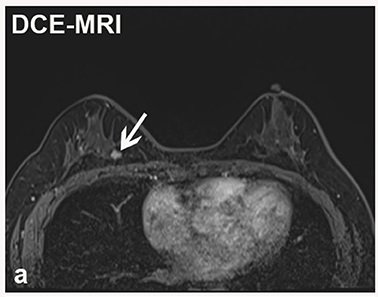

MRI is a medical imaging technique that uses strong magnets and radio waves to create detailed images of the inside of the body without using radiation. MRIs can pick up on minor abnormalities in breast tissue that mammographies can sometimes miss. MRI technology can be particularly useful for examining dense breast tissue, which is associated with a higher risk of cancer and makes finding tumors more difficult with mammography.

Breast MRIs are often recommended for screening where there is a high risk of cancer or when dense breast tissue makes mammography less viable. MRIs are also employed when cancer has already been diagnosed to monitor disease progression and treatment efficacy.ย When results from other imaging techniques like mammography or ultrasounds are inconclusive, an MRI can help by providing more detailed images. MRIs are also used to assess the integrity of breast implants.